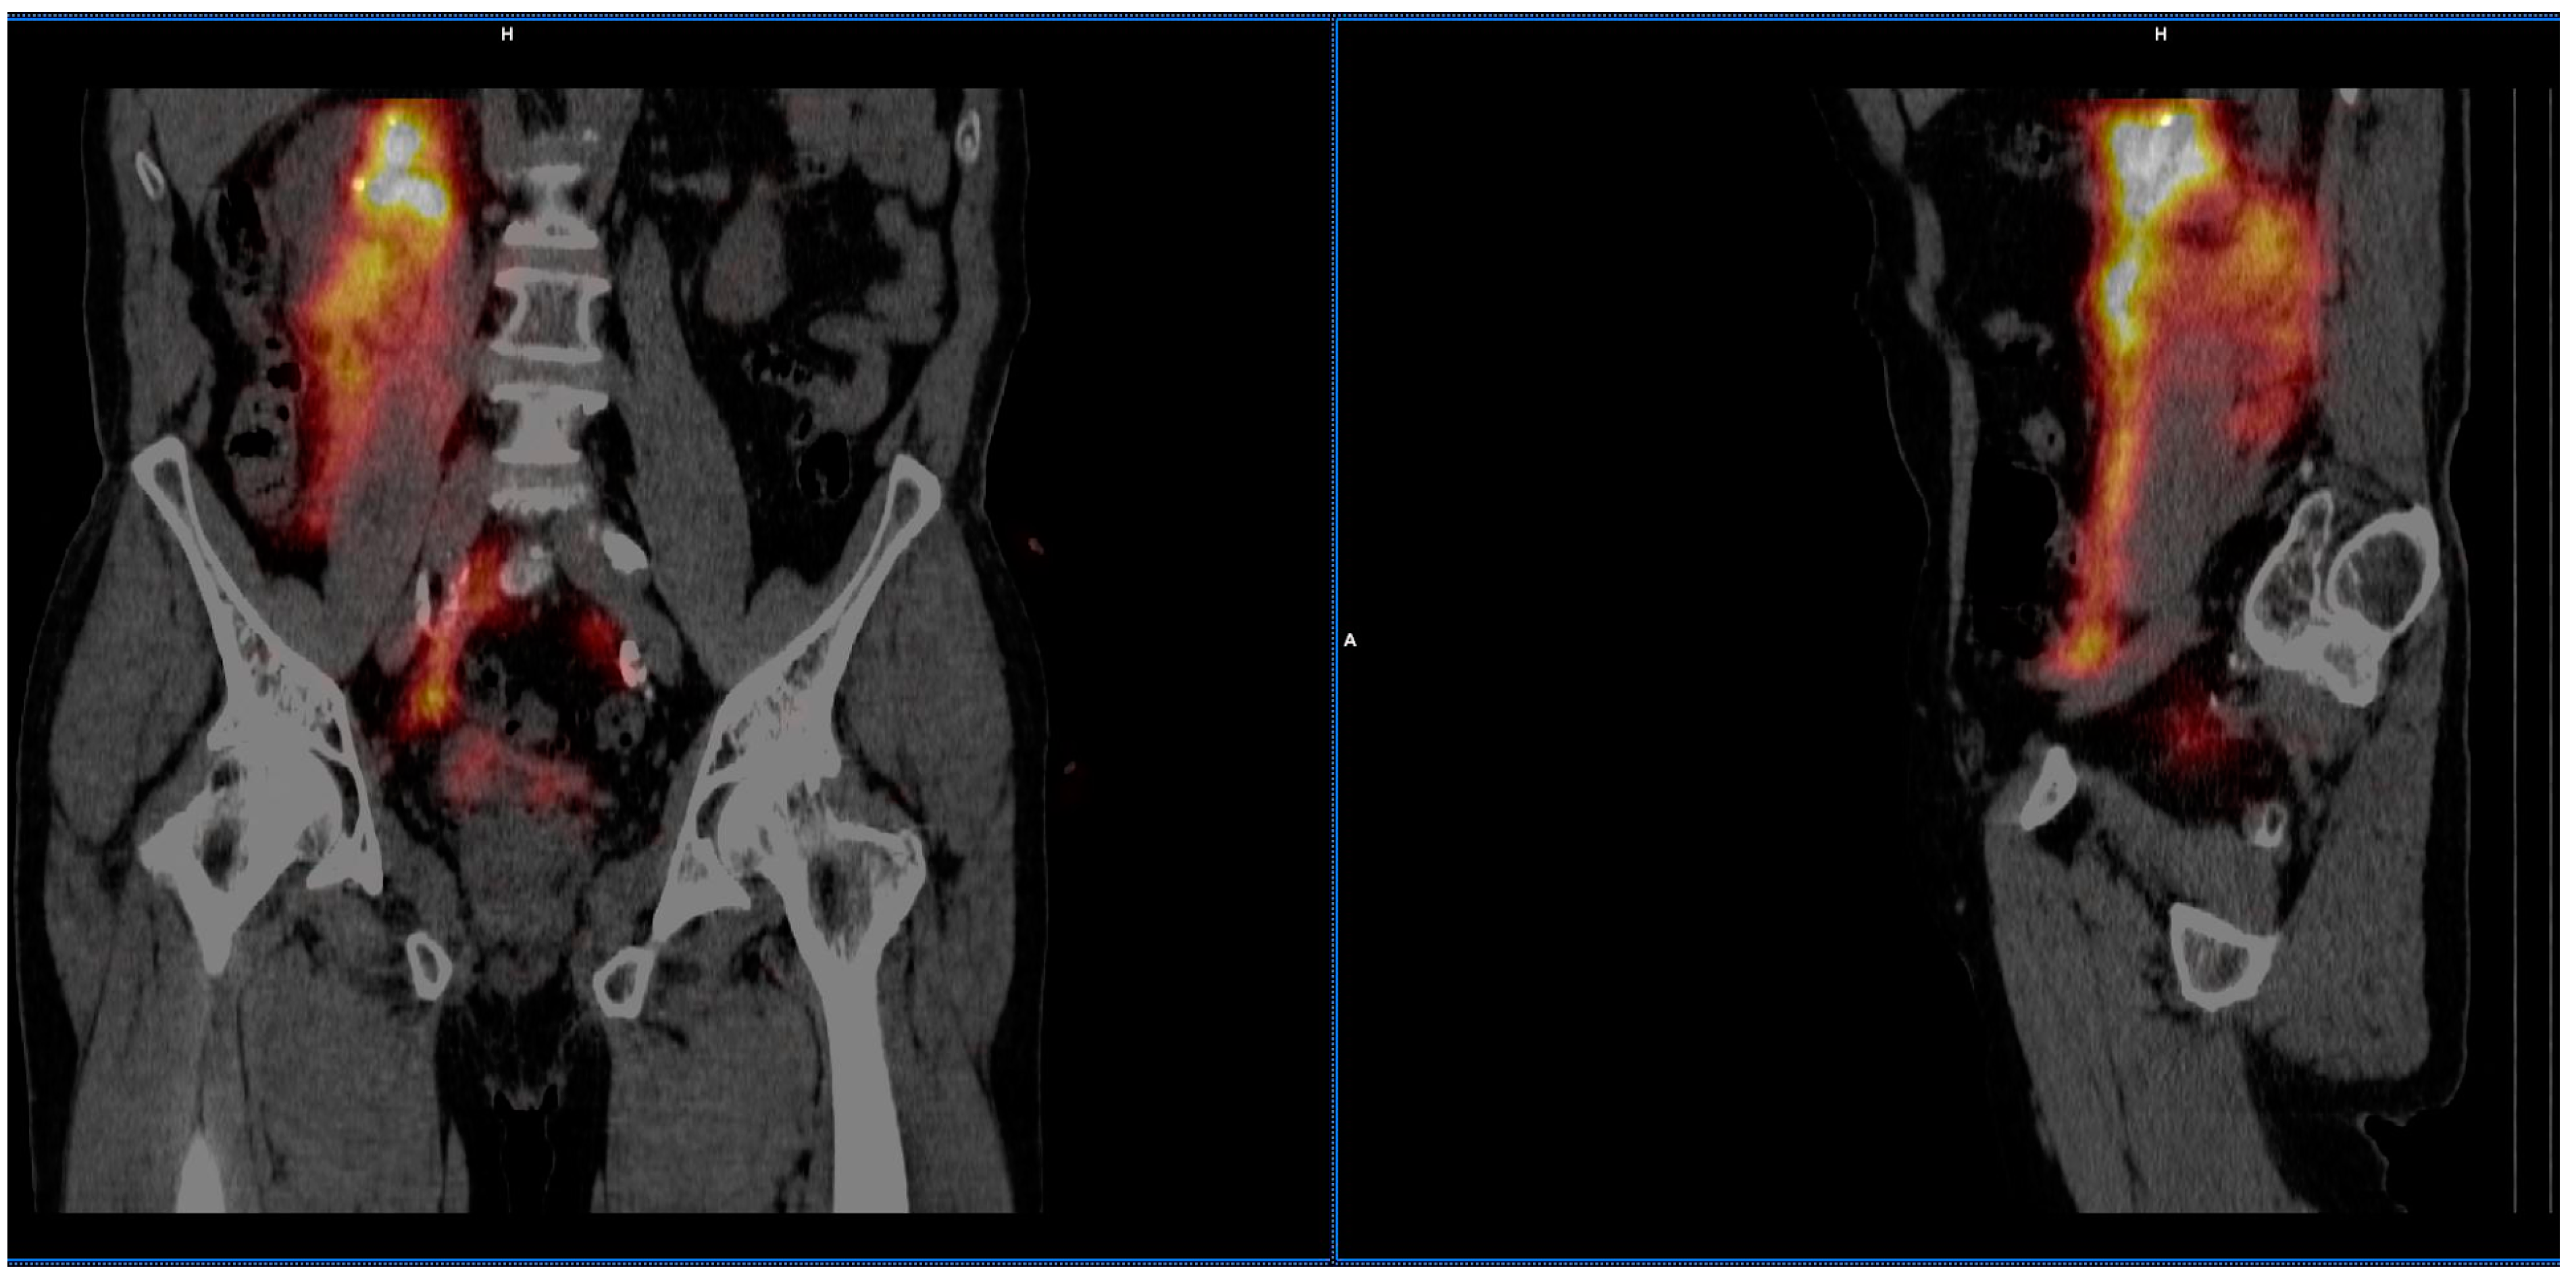

| Lymphatic outflow analysis | |

| Number of patients with identified SLNs | 2 (10.5%) |

| Number of patients with no lymphatic outflow | 17 (89.5%) |

| Number of identified SLNs | 2 (10.5%) |